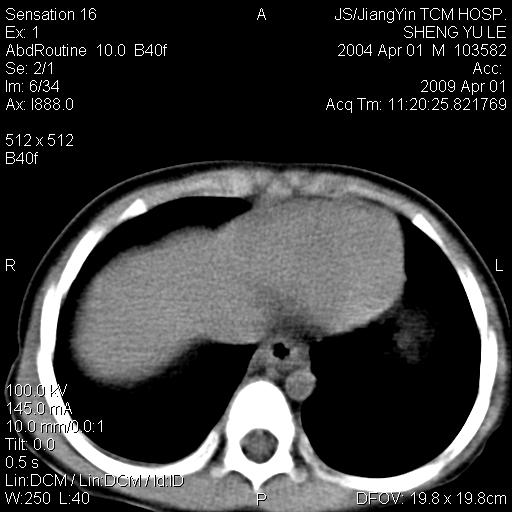

m,5岁。尿痛尿频数天。既往无病史。ct平扫腹盆腔积液。膀胱壁明显增厚。另可见心包增厚。wbc5万,骨髓穿等结果。请指教。

膀胱影像表现结合临床应该是急性膀胱炎症,但为什么有腹水呢?双肾输尿管无扩张,泌尿系压力应该不大不至于引起尿外渗,应该是腹膜感染引起的,但楼主没有提及相关症状,腹膜及膀胱结核?患者白细胞5万(结核不至于这么高啊),脾脏增大,是不是有白血病?进一步检查。。

综合观察分析考虑恶性病变

腹水,膀胱壁增厚,wbc5万,结合临床,支持感染性疾病---感染性腹膜炎、腹水,急性膀胱炎,败血症。期待结果。